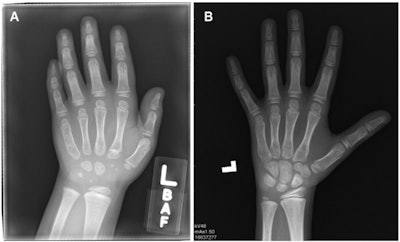

Sample examinations in the study. (A) Computed radiograph in a girl randomly assigned to the control group at center 2 with low AI error and high radiologist error (AI = 46 months, chronologic age = 76 months, radiologist = 69 months, panel = 41 months). (B) Computed radiograph in a boy randomly assigned to the control group at center 4 with high AI error and low radiologist error (AI = 126 months, chronologic age = 140 months, radiologist = 105 months, panel = 100.5 months). Images and caption courtesy of the RSNA.

Sample examinations in the study. (A) Computed radiograph in a girl randomly assigned to the control group at center 2 with low AI error and high radiologist error (AI = 46 months, chronologic age = 76 months, radiologist = 69 months, panel = 41 months). (B) Computed radiograph in a boy randomly assigned to the control group at center 4 with high AI error and low radiologist error (AI = 126 months, chronologic age = 140 months, radiologist = 105 months, panel = 100.5 months). Images and caption courtesy of the RSNA.The study sites included the following: Harvard Medical School and Boston Children's Hospital, Cincinnati Children's Hospital Medical Center, Children's Hospital of Philadelphia, New York University School of Medicine, Stanford University School of Medicine, and Yale University School of Medicine.